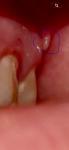

На верхней десне что-то появилось

Добрый, день беспокоит такая проблема вот уже 3 день как на верхней челюсти на десне с лева между 7 зубом и там где должен быть 8 зуб. Но его у меня нету с лева еще не вылез а вот с права есть. В сентябре лечил зубы 5 и 6 делали кт верхней челюсти врач говорил что повезло что зубы мудрости ровно растут. Вообщем касательно симптомов то есть такое как не чувство давление а больше точечная боль, когда задеваю то место щекой или если левую часть лица напрягаю. По внешнему виду, оно что ли белое и свисает. А на ощуп выпуклость что ли.